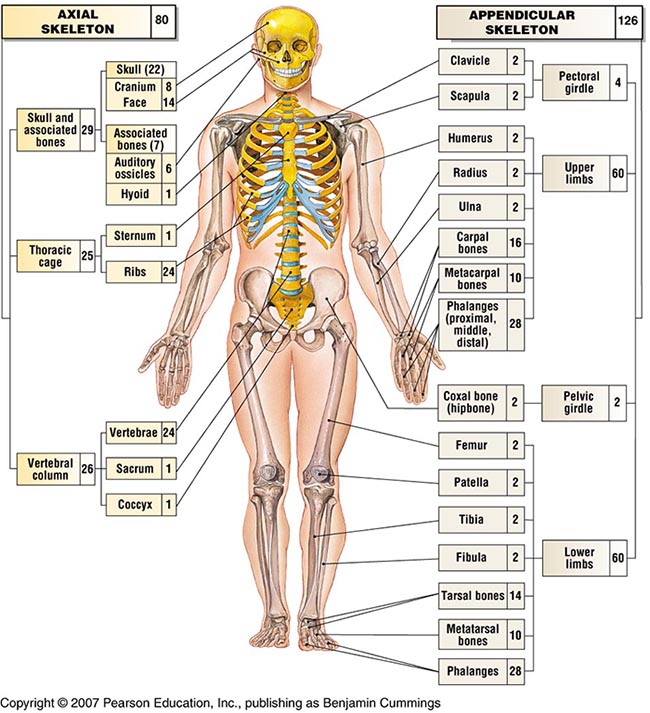

ระบบร่างกายของมนุษย์และสัตว์ :: ระบบโครงกระดูกและกล้ามเนื้อ โรคน้ำกัดเท้า – TALON

ระบบกระดูก: ระบบกระดูก กระดูก เท้า ผิด รูป รักษา, โรคนิ้วโป้งเท้าเอียง – อาการและการรักษา …